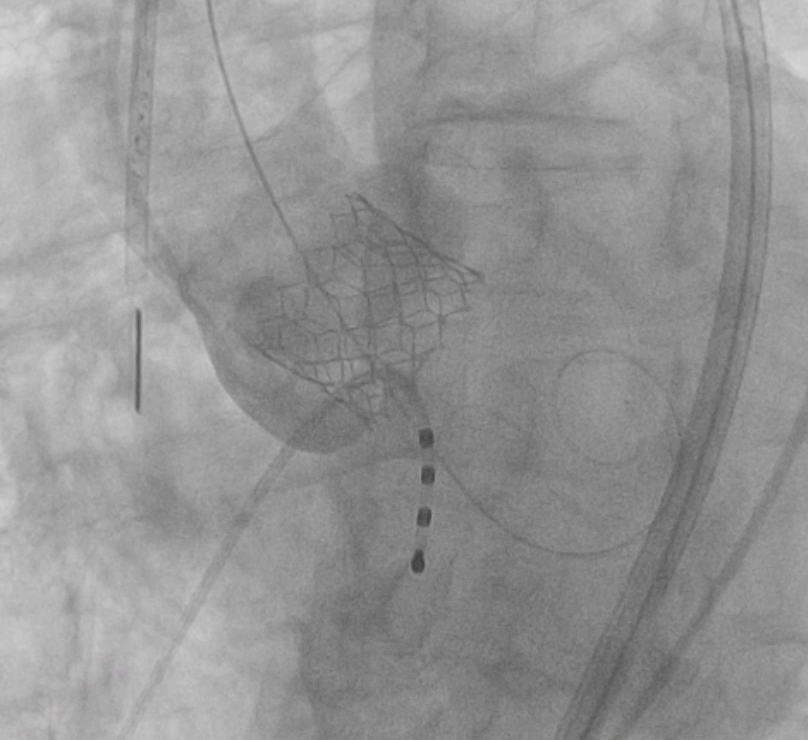

Under general anesthesia, arterial and venous access were obtained via the right femoral artery and vein. A temporary pacing lead was inserted for rapid pacing; however, consistent capture could not be achieved under fluoroscopic guidance. Therefore, intracardiac echocardiography (ICE) was advanced into the right heart to allow precise, close-range localization of the pacing lead. ICE was continuously used to provide real-time monitoring of valve positioning, implantation depth, and the spatial relationship between the transcatheter valve and the membranous septum. A 26-mm Sapien 3 valve was successfully deployed under temporary pacing. Post-deployment angiography and ICE confirmed optimal valve position without conduction disturbance, paravalvular leak, or other complications. The mean aortic valve pressure gradient decreased from 35.5 to 11.2 mmHg. The patient recovered uneventfully after the procedure.

TAVI deploy.PNG